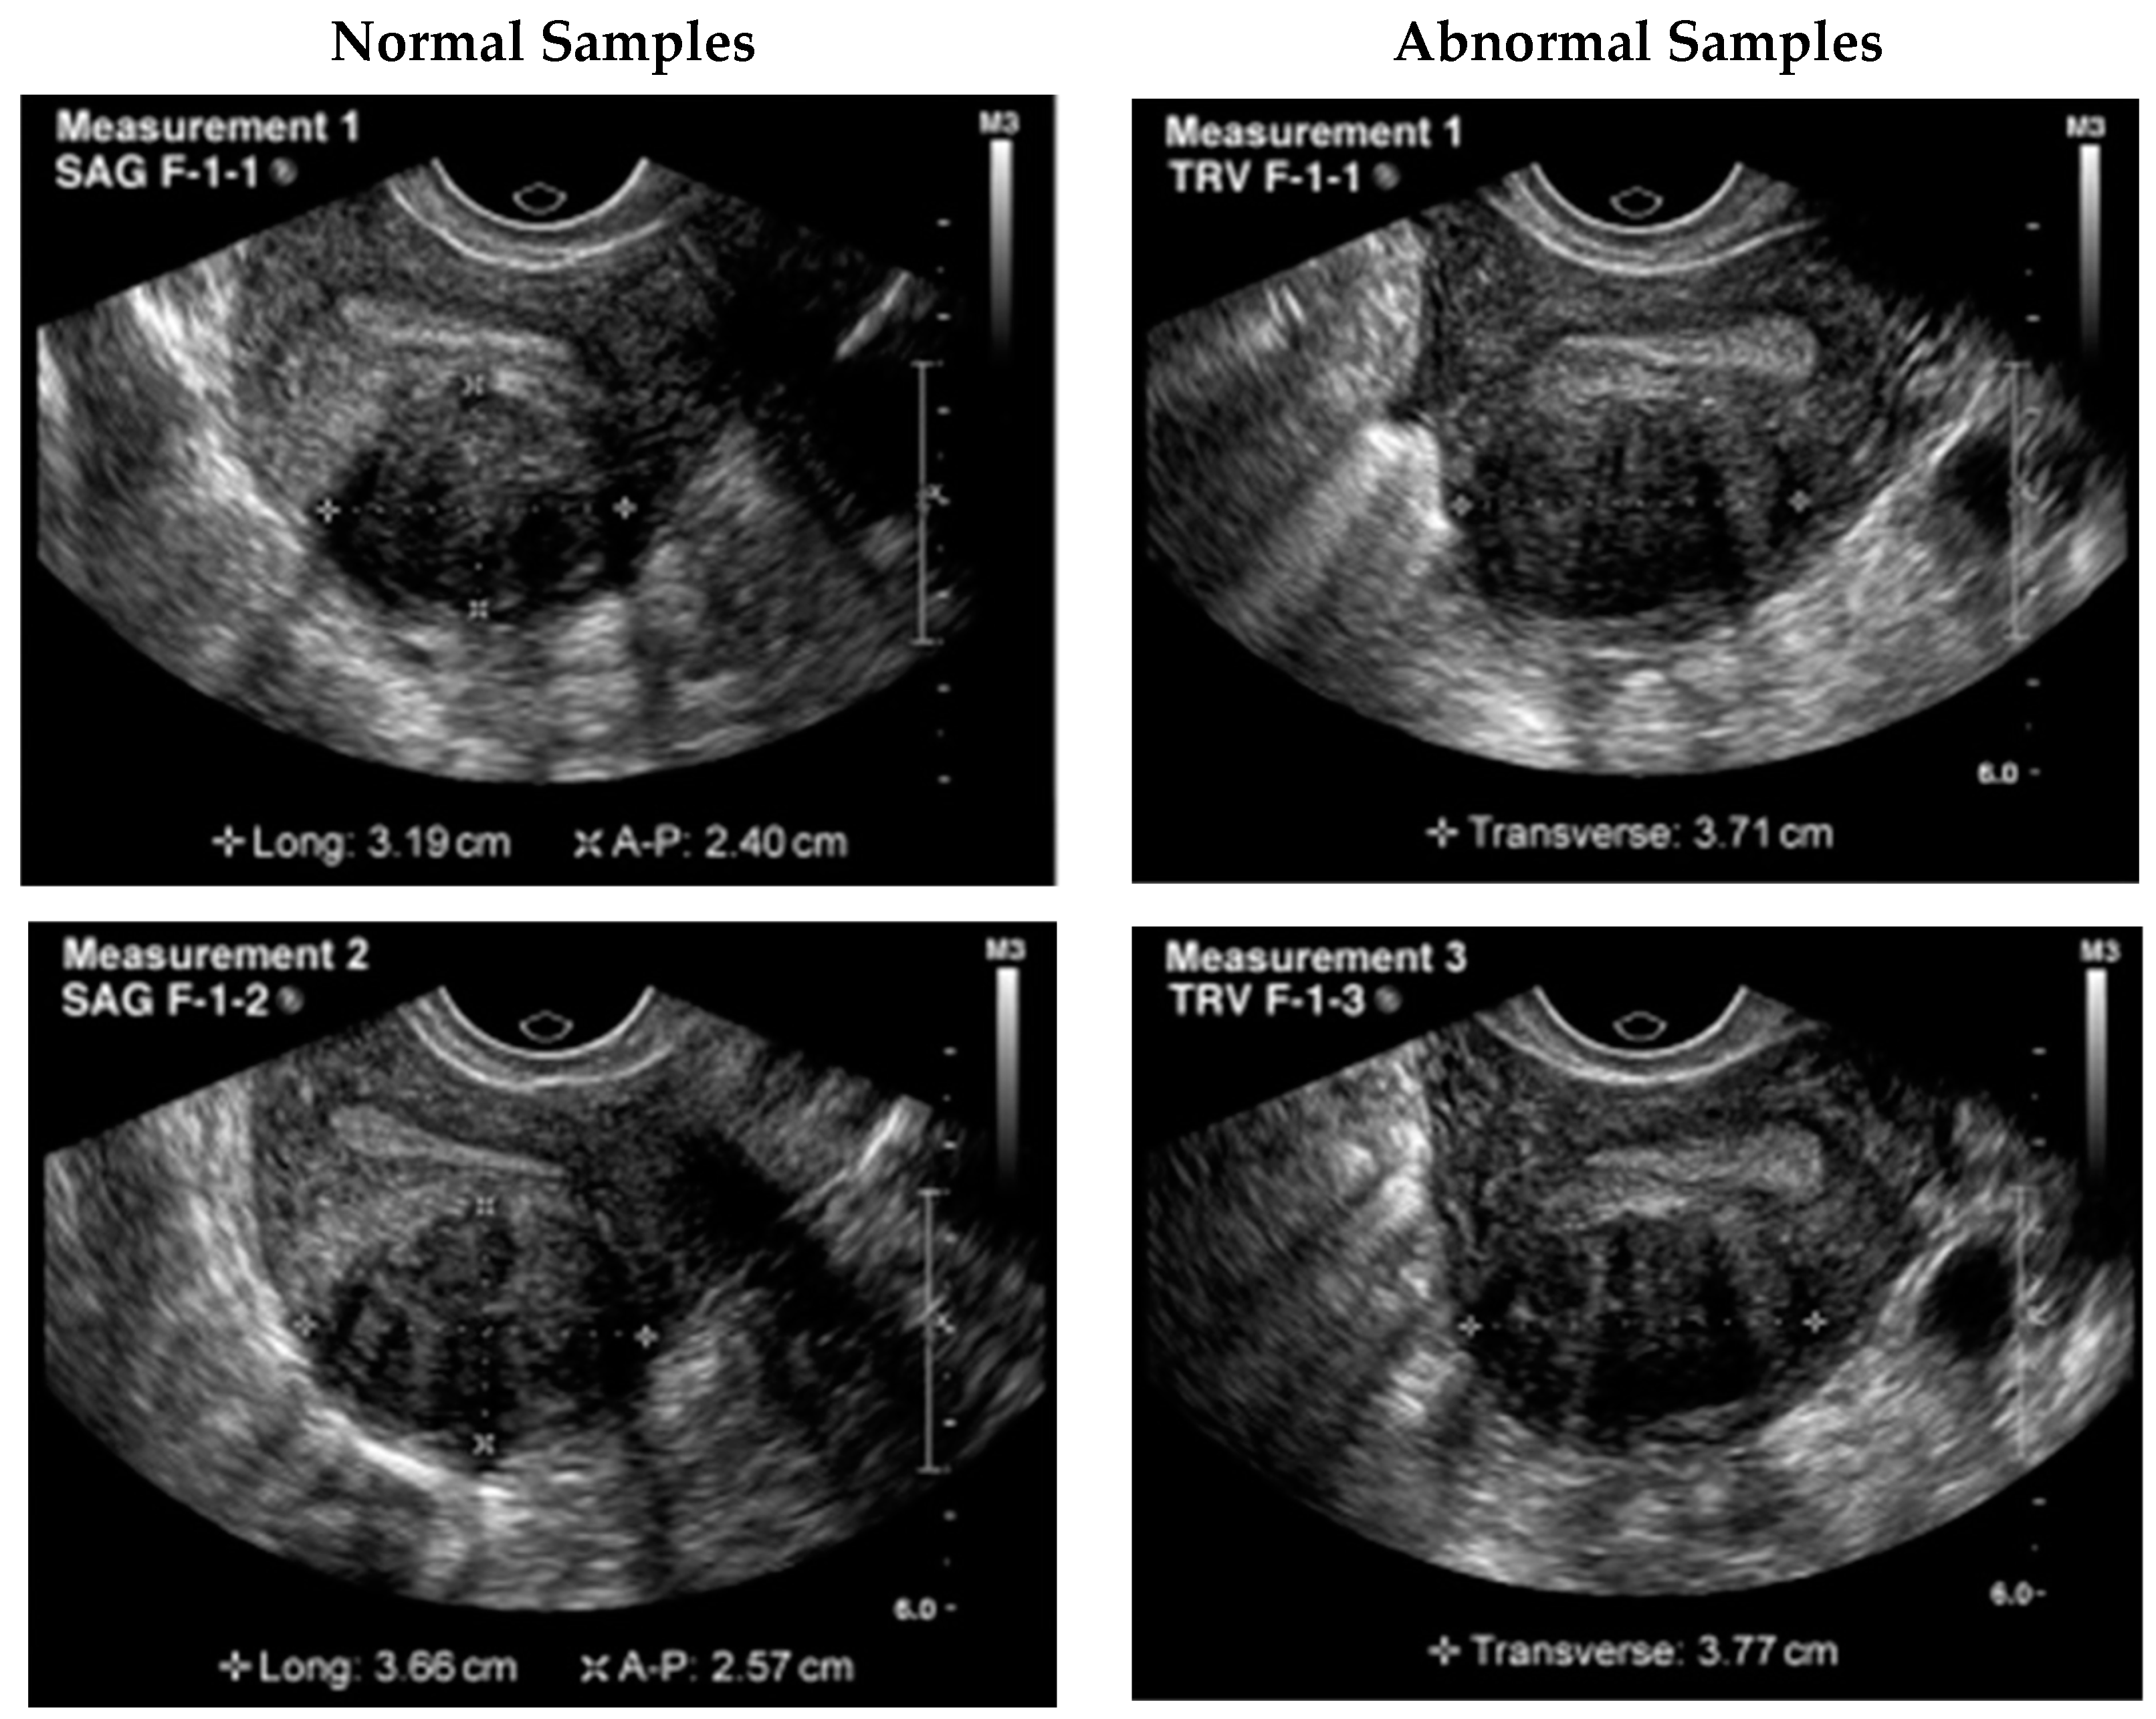

Manual identification of UF in ultrasound images is a laborious process that might vary from observer to observer. As reported in studies [7,8,9], significant progress has been made in the use of deep convolutional neural networks (DCNN) for automated medical image analysis tasks such as tumor detection and classification in ultrasound images. In Figure 1, a UF ultrasound scan is displayed with the region of interest (ROI) outlined in a square. These advances have the potential to improve patient outcomes by allowing for more precise, efficient, and reliable detection of UF in ultrasound images.

Figure 1. Ultrasound image of benign tumor of uterine fibroids.